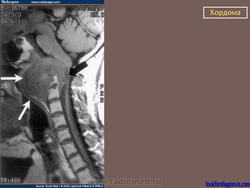

Хордома развивается из персистирующих остатков хорды. Преимущественная локализация хордомы - это область сфеноокципитального сочленения и крестцово-копчиковый отдел позвоночника. Сведения о частоте отдельных форм хордомы весьма разноречивы.

Для хордом различных локализаций, выявлены наиболее характерные симптомы. Так, селлярные хордомы чаще проявляются глазодвигательными нарушениями (III нерв - 43%, VI нерв - 59%), и у трети больных эндокринными нарушениями (чаще гипотиреоз, гипокортицизм, гипогонадизм). У больных с хордомами ската типичными симптомами были поражение отводящего (79%), тройничного нерва (65%) и туловищная атаксия (55%). Симптомы поражения VII, VIII, IX или X черепных нервов были у трети больных с этой локализацией опухоли. Клиника при локализации хордом в краниовертебральной области представлена, как правило, характерным симптомокомплексом. Поражаются черепные нервы с VI по XII (VI -53%, VII - 33%, VIII - 27%, IX и X - 77%, XI - 48%, XII - 62%), у части больных имеют место тетрапарез или гемипарез. Нередко обращает на себя внимание вынужденное положение головы или ограничение объёма движений (поворотов и наклонов головы), боль и "хруст" в шее.